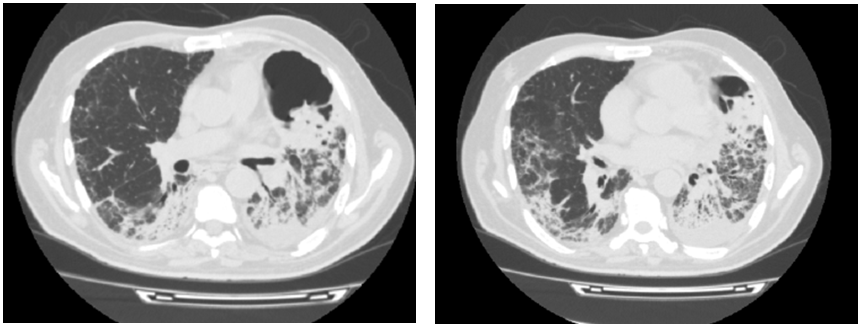

At admission, the patient had acute respiratory failure. Arterial blood gas analysis with oxygen 8 L/min showed a PaO2 of 67 mmHg, PaCO of 31 mmHg, pH of 7.47, and HCO3 of 23mEq/L. A thoracic radiograph showed multiple pulmonary infiltrates consistent with interstitial lung disease (Figure 2). Echocardiogram showed normal left ventricular function. Laboratory investigations revealed neutrophilic leukocytosis (white blood cells 14200/UL, neutrophils 11640/mL, lymphocytes 1670/mL); elevated sedimentation rate 136 (<20 mm/h); elevated lactated shydrogenase (LDH),313 U/L; creatine phosphokinase (CPK) level,24 U/L (0–195 U/L) aspartate aminotransferase (AST) level, 15 U/L (6–34 U/L); alanine transaminase (ALT) level, 16 (6–34 U/L); and C–reactive protein, 44 mg/dL (0–5 mg/dL). HIV test was negative.

Figure 2 Multiple pulmonary infiltrates consistent with interstitial lung disease.